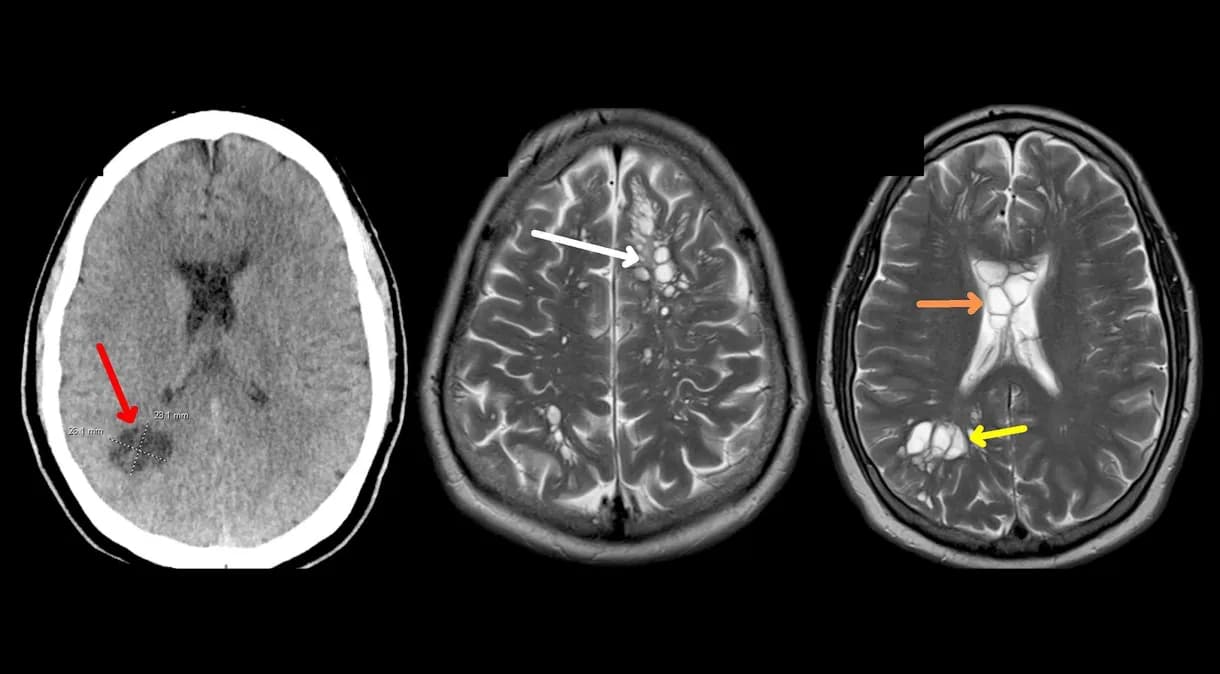

O homem foi ao médico porque suas dores de cabeça estavam ficando muito fortes e frequentes, acontecendo quase toda semana. E o remédio para dor de cabeça não estava ajudando. Quando fizeram um exame de imagem do cérebro dele, viram muitos cistos, que são como bolsinhas cheias de líquido.

A princípio, os médicos pensaram que ele poderia ter uma doença rara no cérebro e o mandaram para um hospital em Orlando para ser consultado por um especialista. Mas, depois de exames específicos, eles perceberam que havia uma infecção causada por larvas de tênia no cérebro, uma doença chamada neurocisticercose.

Depois de descobrir o problema, o homem foi tratado com remédios para tirar os parasitas e as dores de cabeça dele passaram. Os cistos no cérebro dele também diminuíram.